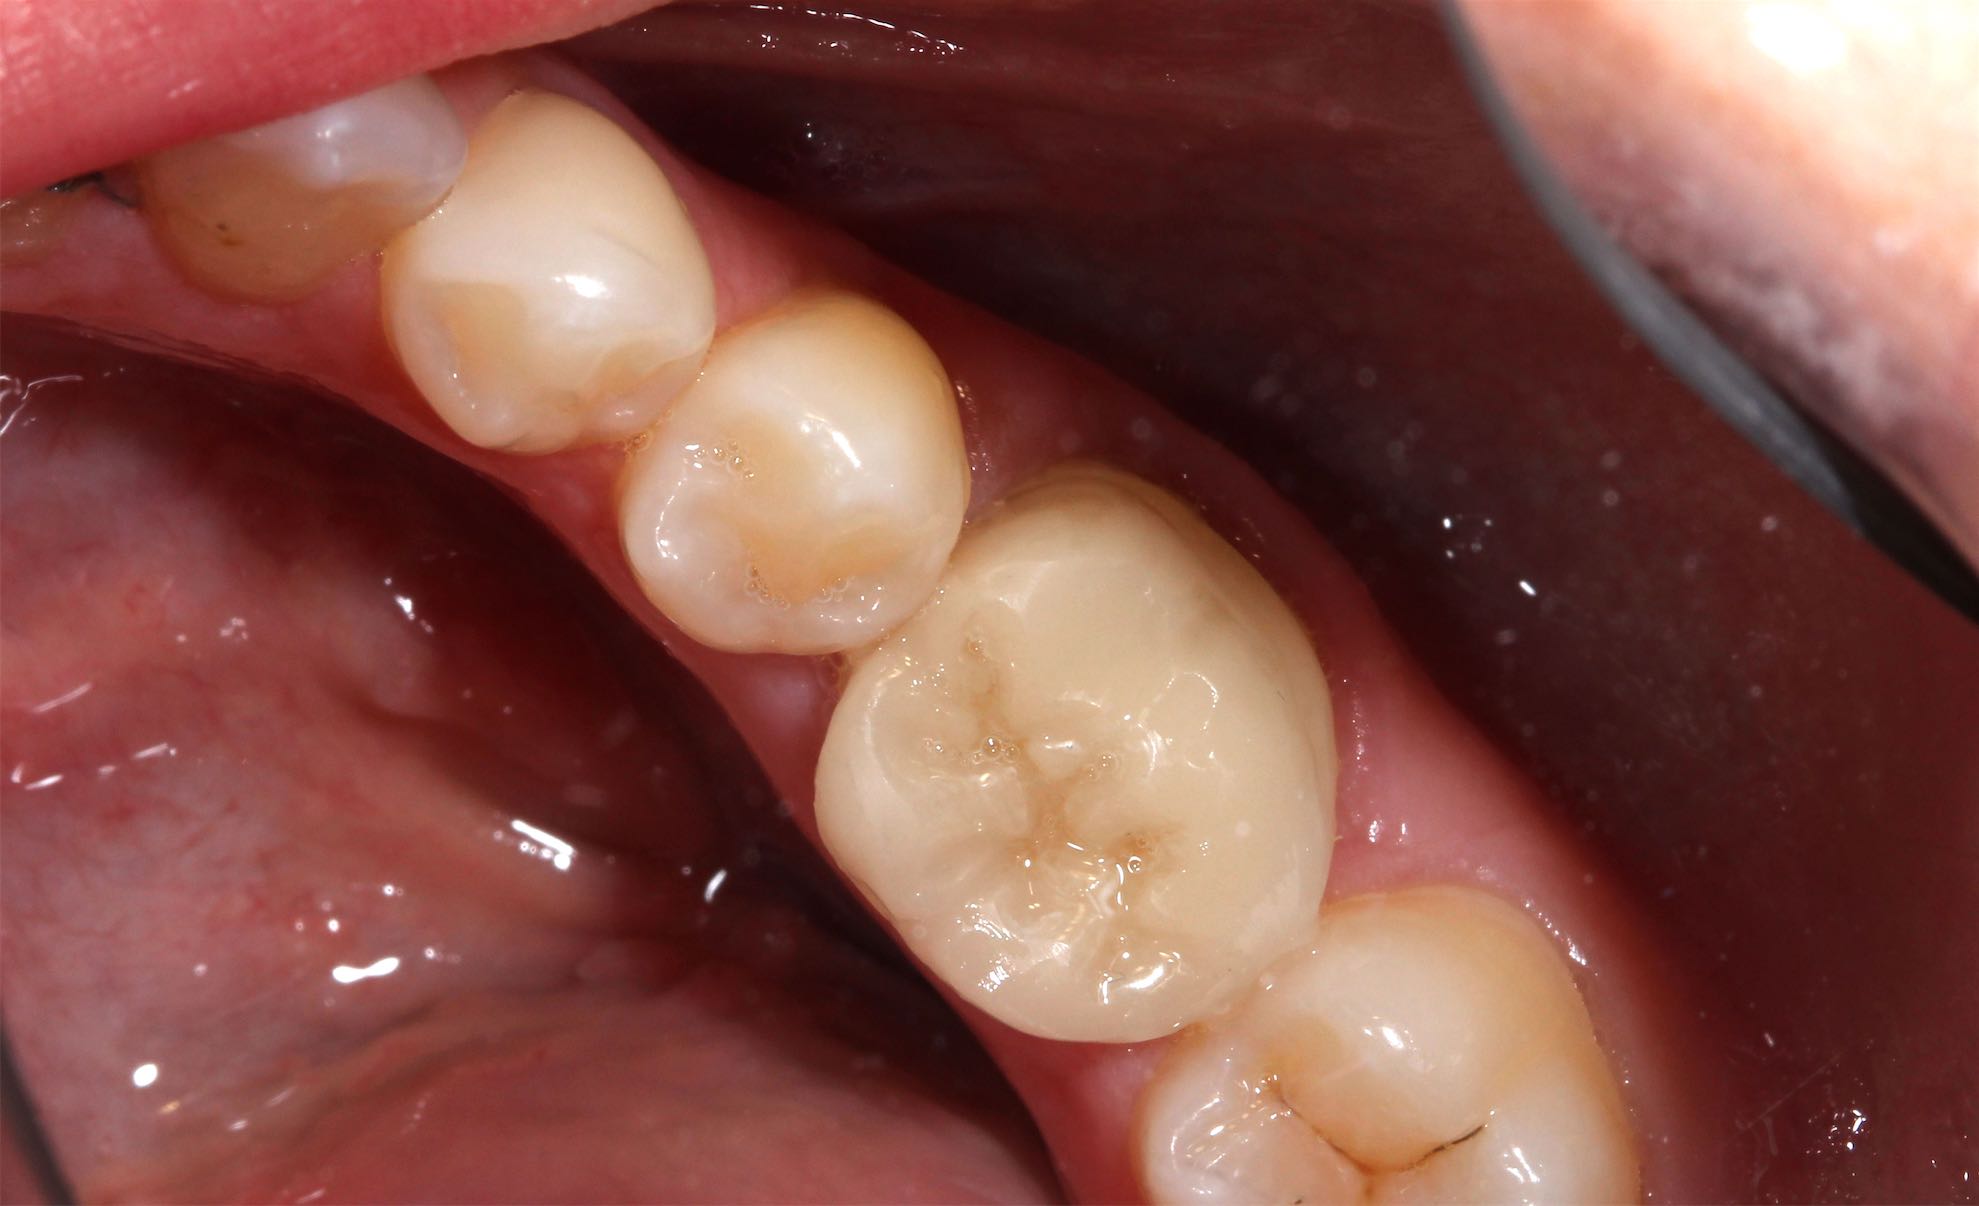

Odontología Restauradora Incrustaciones CAD-Cam

BeforeAfter